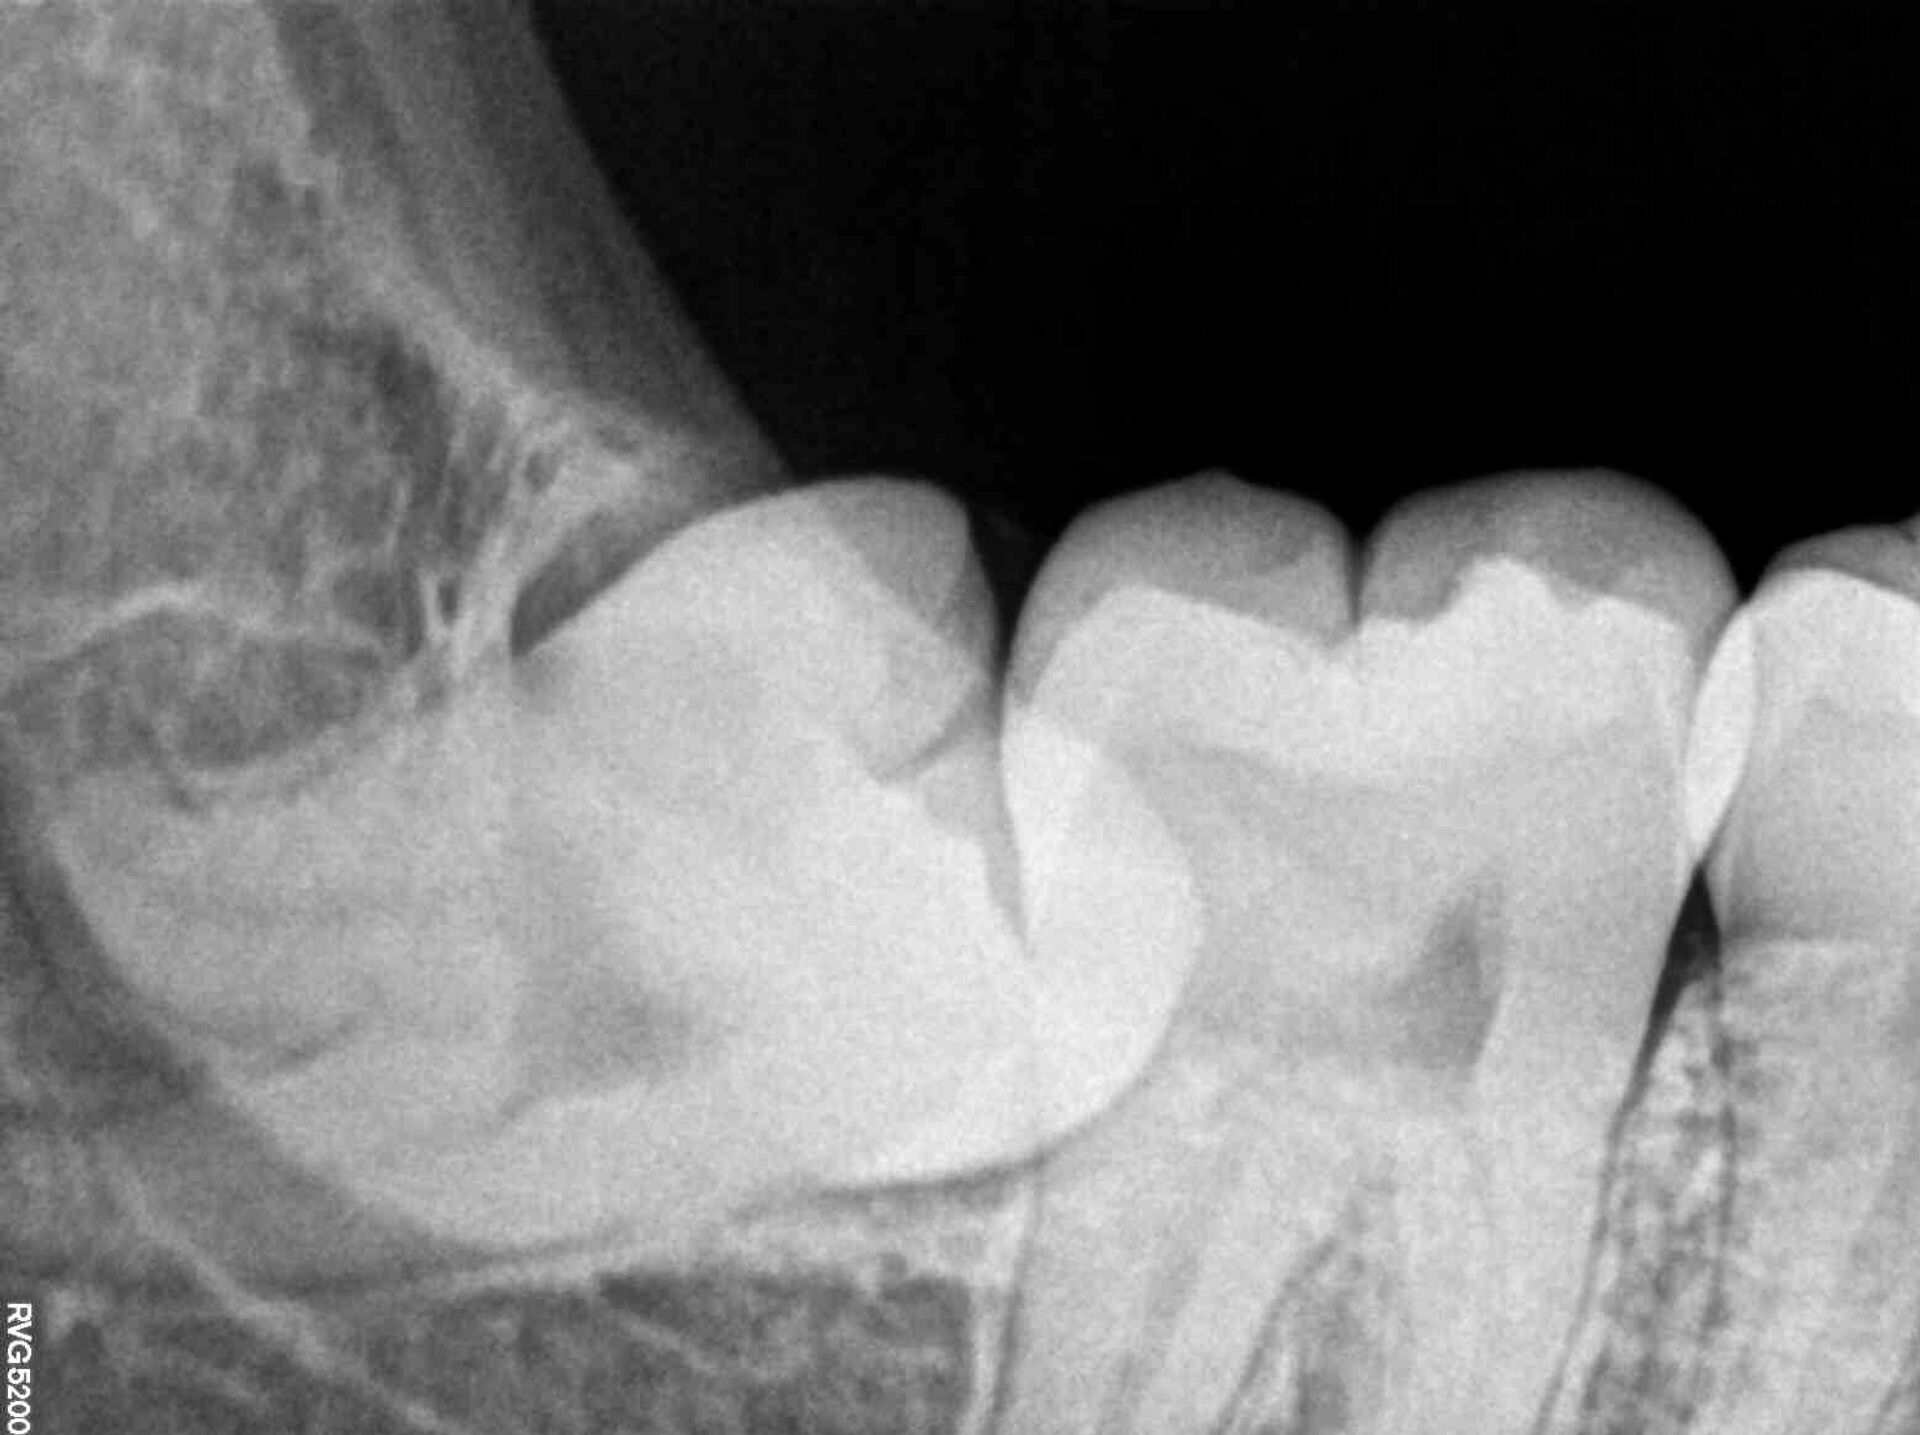

Anomalías de la mandíbula. Las muelas extremas pueden causar agrupamiento de la fila de dientes. Con más frecuencia que otras unidades se desvían de su posición natural. Ese tipo de molares se denominan molares distópicos. En caso de distopía grave, se extraen y se prescribe una terapia de ortodoncia para restaurar la estética y la funcionalidad de los dientes.

Retención. A menudo ocurre que la unidad no aparece en absoluto. Tanto la raíz como la corona permanecen bajo la superficie de la encía, completamente formadas. Parecería que no hay diente, lo que no reviste un problema, pero las muelas de juicio retenidas pueden dañar las raíces de los molares vecinos o afectar a las terminaciones nerviosas.

Una extracción compleja se produce cuando el diente aún no ha erupcionado del todo o tiene las raíces torcidas y ramificadas. Asimismo, hay casos en los que la corona del molar está muy dañada, lo que dificulta bastante su agarre con fórceps.

En algunos casos, luego de la anestesia, el médico tiene que hacer una incisión en el tejido gingival, así como perforar el tejido óseo o perforar el diente. Una extracción compleja necesariamente se completa con sutura.